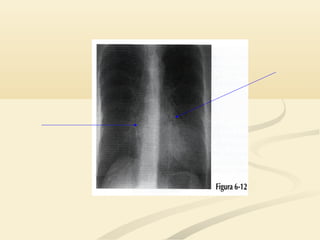

Corazón/aorta ascCorazón/aorta asc AortadescendenteAorta descendente

 Borde cardíacosuperior derecho y la aorta ascendenteBorde cardíaco superior derecho y la aorta ascendente son estructuras anteriores en el lado derecho.son estructuras anteriores en el lado derecho.  La aorta descendente es posterior en el lado izquierdo.La aorta descendente es posterior en el lado izquierdo.  La tráquea y el botón aórtico están localizadas en elLa tráquea y el botón aórtico están localizadas en el tórax mediotórax medio